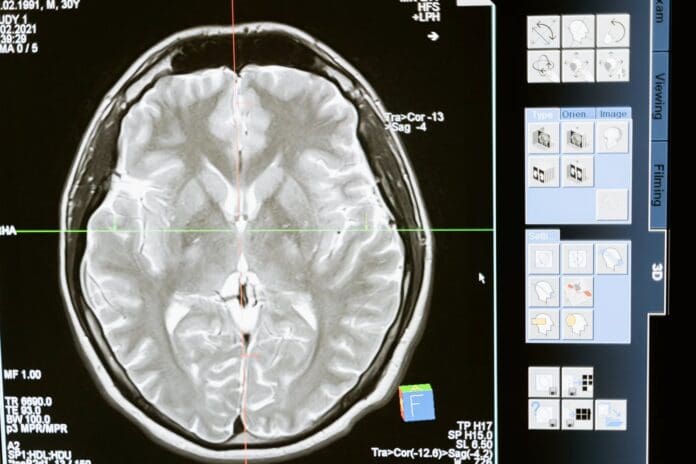

Sophie Cope, medical negligence solicitor for JF Law, said: “Radiology is a key part of modern healthcare and includes diagnostic tests such as X-rays, MRI scans, CT scans and ultrasounds. These tools are a vital step in identifying a patient’s condition and ensuring they receive the appropriate treatment.

“When something goes wrong at this stage, whether a scan is carried out to a poor standard, misinterpreted, delayed, or never carried out in the first place, the impact on a patient’s health can be profound.”